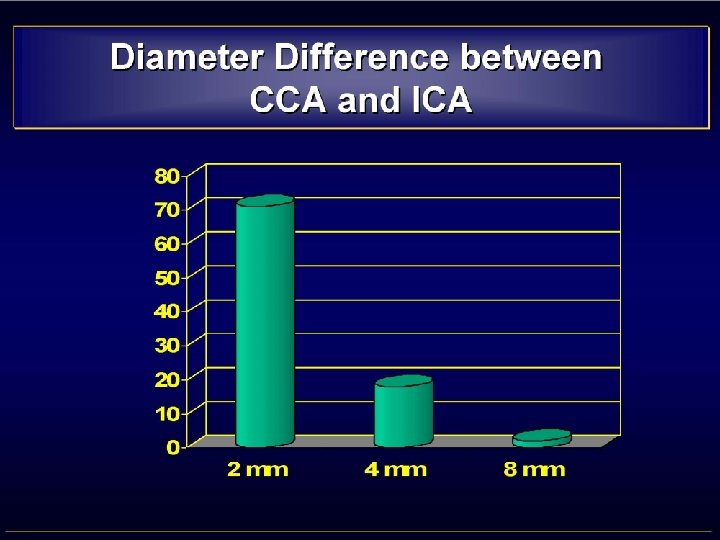

• MISMATCH CCA-ICA